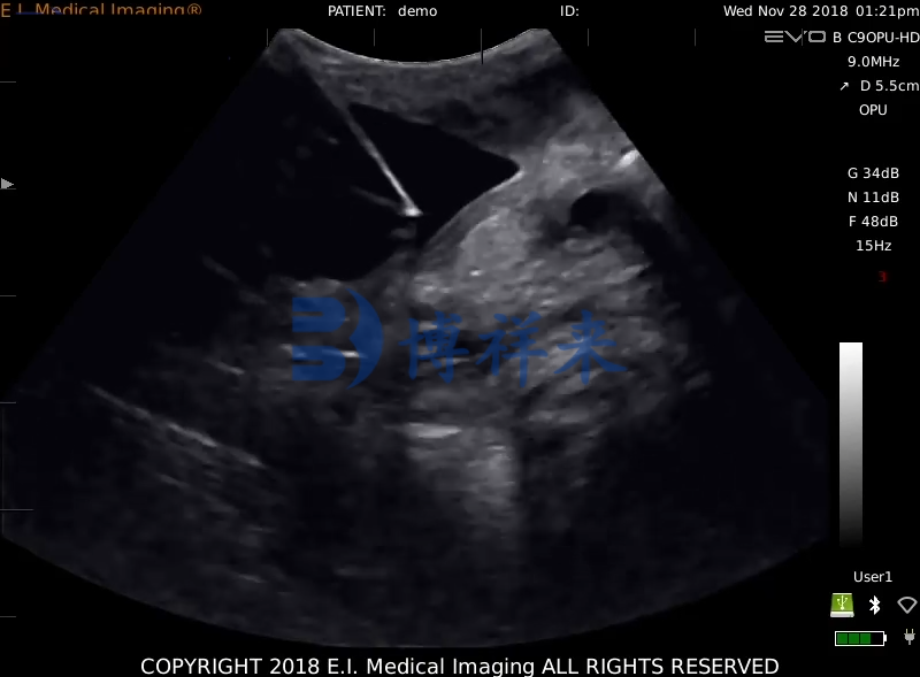

产品影像图

• 马活体采卵

2、操作人员一手拿探头一手通过直肠对卵巢进行牵引,把卵巢牵引到贴在探头上,使得我们能在EVO显示屏上清楚的看到卵巢,根据图像区分卵泡和CL,调整B超探头和卵巢的位置使监视器上卵泡位于穿刺针直线的延长线上时,推进穿刺针对卵泡进行穿刺.同时,用脚踏开关控制真空泵抽取卵泡液,真空泵的压力在60~80mm汞柱之间调整。

3、从监视器上可以观察到被抽取卵泡液和卵泡开始缩小,变得不规则,黑色的影像变成了亮片,直到卵泡在图像上消失,退出穿刺针,再对第二个卵泡进行穿刺,抽取卵泡液,直到该侧卵巢上2ram以上的卵泡被穿刺完后,调整探头以相同的方法对另一侧卵巢的卵泡进行穿刺。最后,所有符合条件的卵泡都被穿刺完后,用含有肝素的PBS液冲洗采卵针及导管,冲洗液也方入收集管。